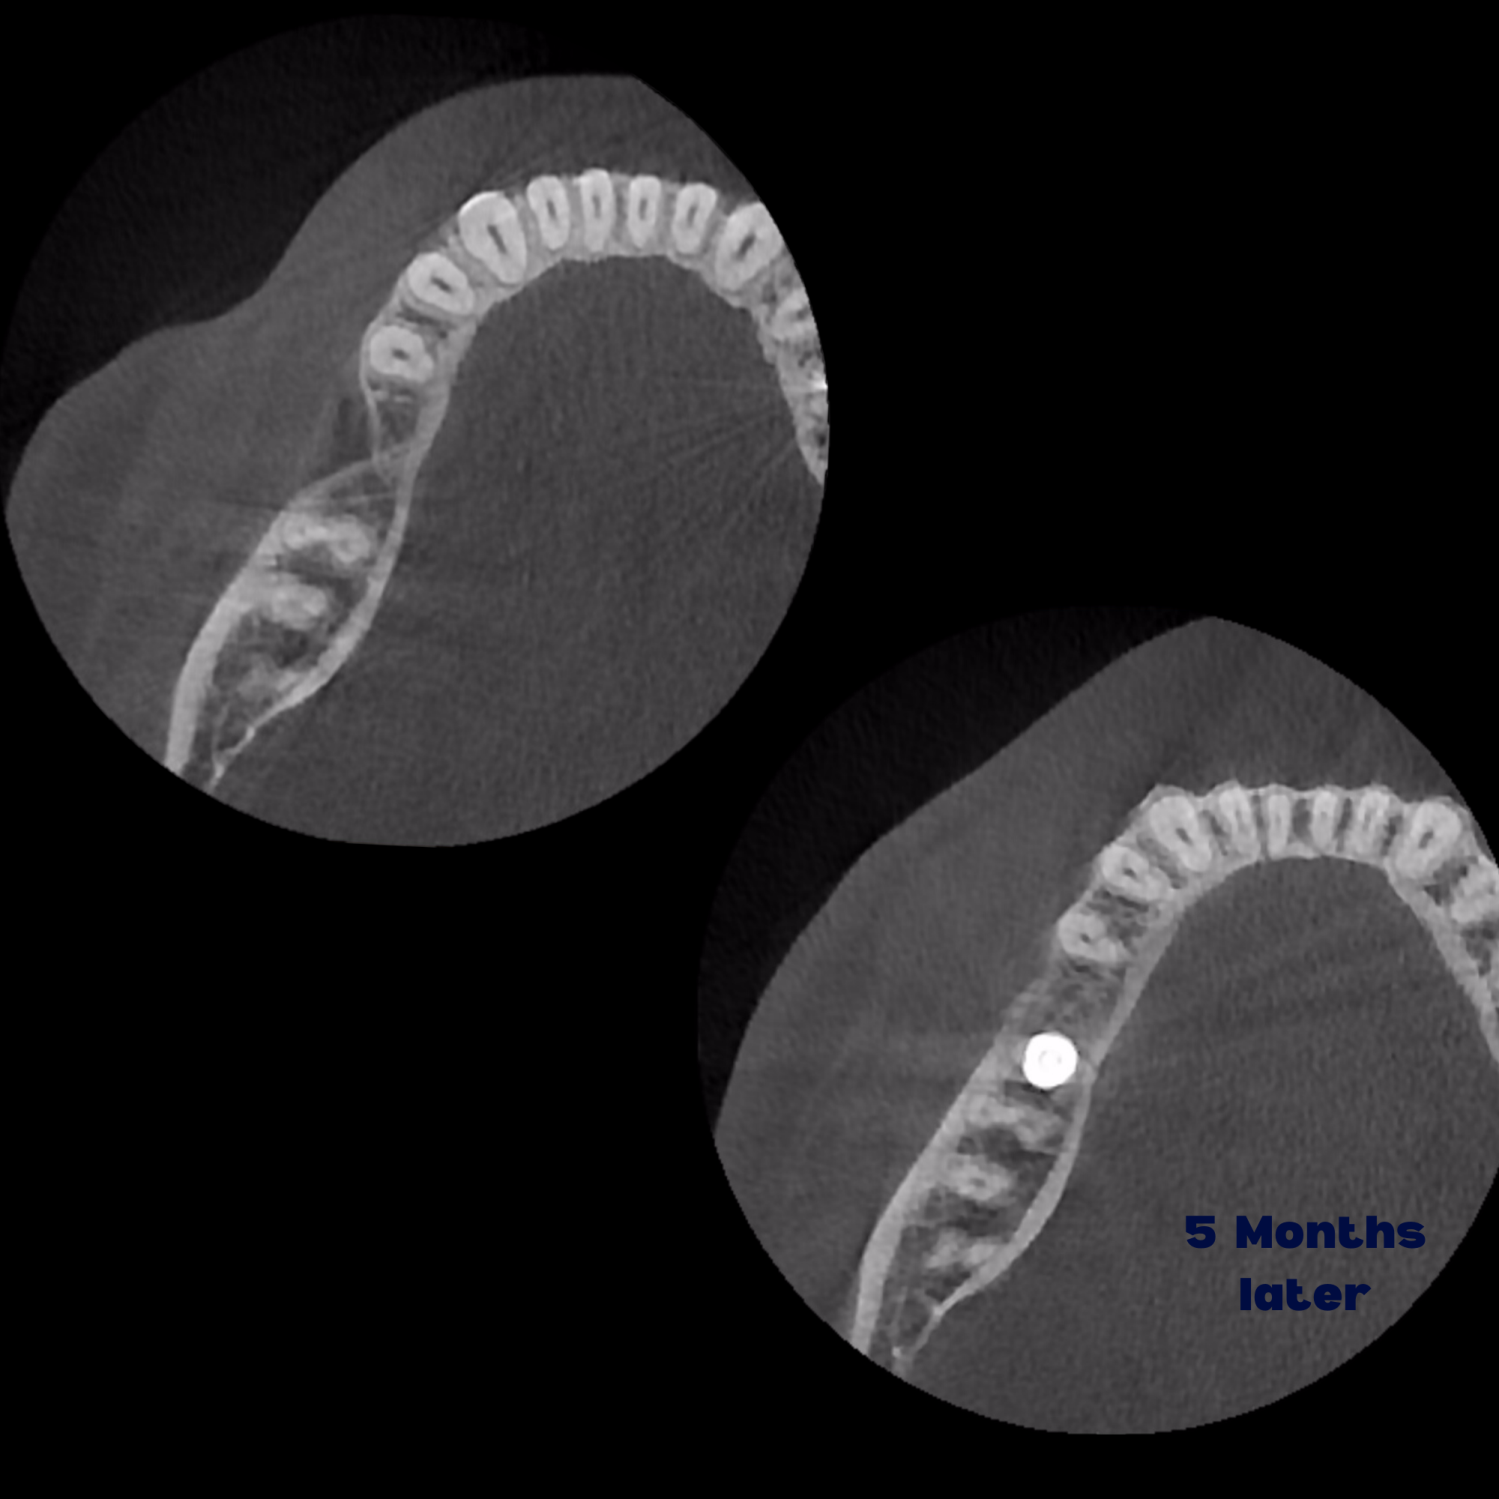

Kist nedeni ile çene kemiğinde defekt oluşmuş vakamıza sert ve yumuşak doku ogmentasyonu uyguladık.